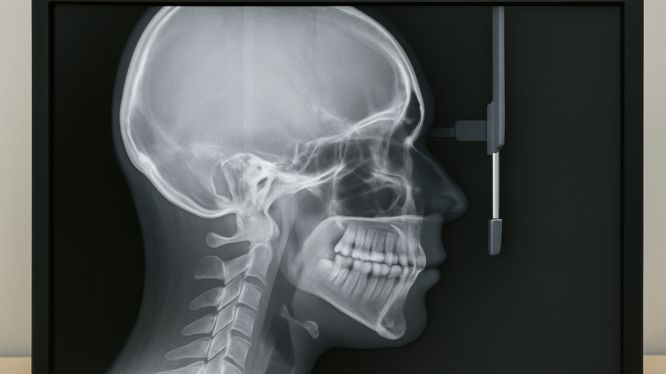

🧠 2. Radiografía Cefalométrica Lateral

¿Qué es?

Una radiografía lateral del cráneo que permite observar con claridad la relación entre el cráneo, el maxilar, la mandíbula y los dientes. También es una herramienta fundamental en ortodoncia para analizar la estructura ósea facial desde una vista lateral completa.

¿Para qué sirve?

✅ Analizar el crecimiento óseo y determinar si el paciente tiene un patrón de crecimiento horizontal, vertical o neutro

✅ Clasificar el tipo de maloclusión: Clase I (normal), Clase II (mandíbula hacia atrás) o Clase III (mandíbula prominente)

✅ Evaluar el perfil facial y los cambios estéticos que pueden lograrse con ortodoncia

✅ Planear tratamientos ortopédicos o quirúrgicos complejos

✅ Comparar cambios antes y después del tratamiento

✏️ Trazado Cefalométrico

De este modo, una vez obtenida la imagen, se realiza el trazado cefalométrico, que consiste en:

📐 Delimitar puntos anatómicos clave del cráneo y los dientes

📏 Dibujar líneas y ángulos que representan relaciones óseas y dentales

📊 Medir proporciones, inclinaciones, distancias y discrepancias

🧠 Identificar alteraciones esqueléticas que requieren ortopedia o cirugía

Además, este análisis puede hacerse de manera manual (sobre la radiografía impresa) o mediante software especializado, como parte de nuestro servicio en Dicorsa. Adicionalmente, los doctores reciben el estudio listo para interpretar y trabajar su plan de tratamiento.

¿Cómo se realiza?

El paciente se posiciona lateralmente en el equipo de radiología, con la cabeza fija en un soporte para evitar movimientos. Así, la toma se realiza en segundos y no causa molestias.

🕒 Duración: menos de 1 minuto

🧑⚕️ Recomendado en adolescentes en crecimiento, casos complejos o cirugías ortognáticas